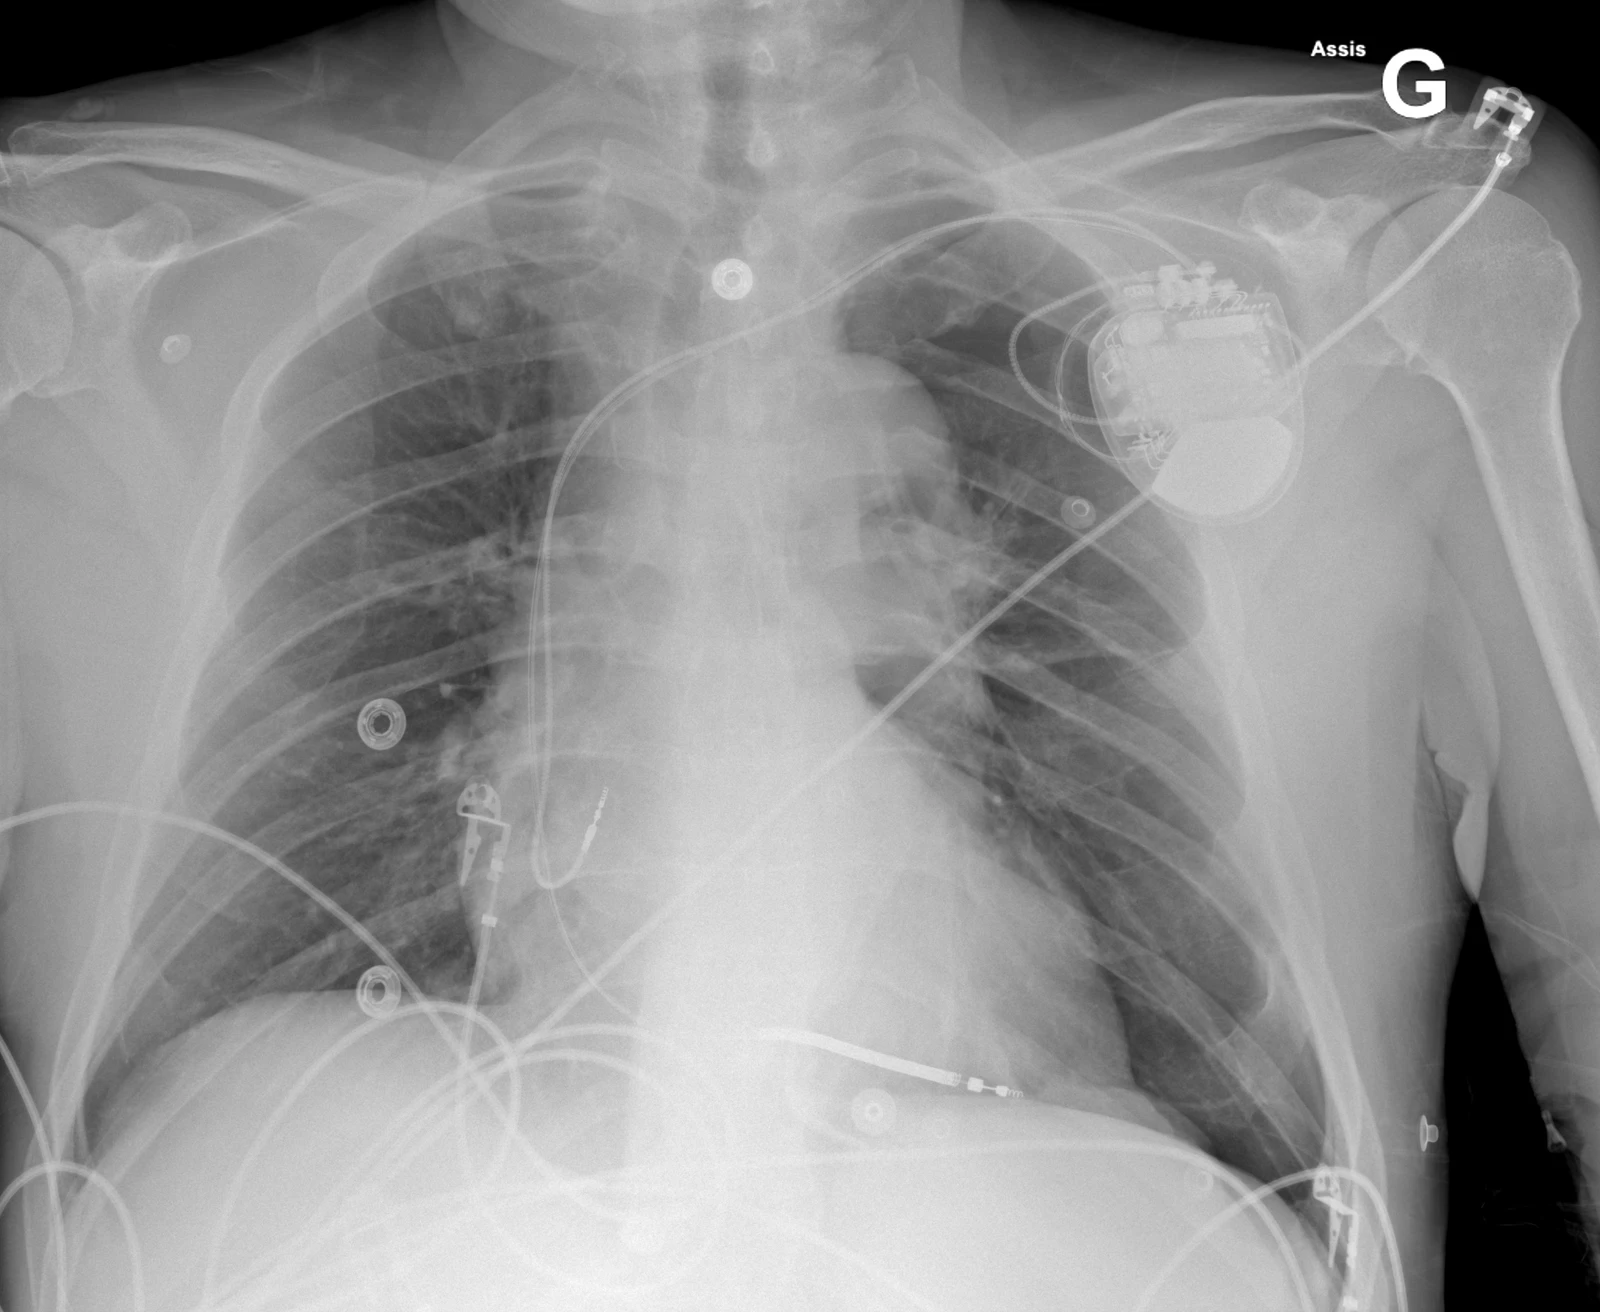

Cette radiographie a été prise chez le même patient après la pose d’un drain thoracique à gauche et montre une disparition radiologique du pneumothorax.

A noter qu’on utilisera si possible un drain de petit calibre (≤ 14 Fr). La voie antérieure (ligne médioclaviculaire) utilisée pour exsuffler un pneumothorax en urgence peu également être utilisée pour poser un drain (de préférence de petit calibre), offrant l’avantage de poser le drain à l’endroit où se trouve l’air. En cas de pose de PM récente, ce dernier peut gêner l’abord antérieur.